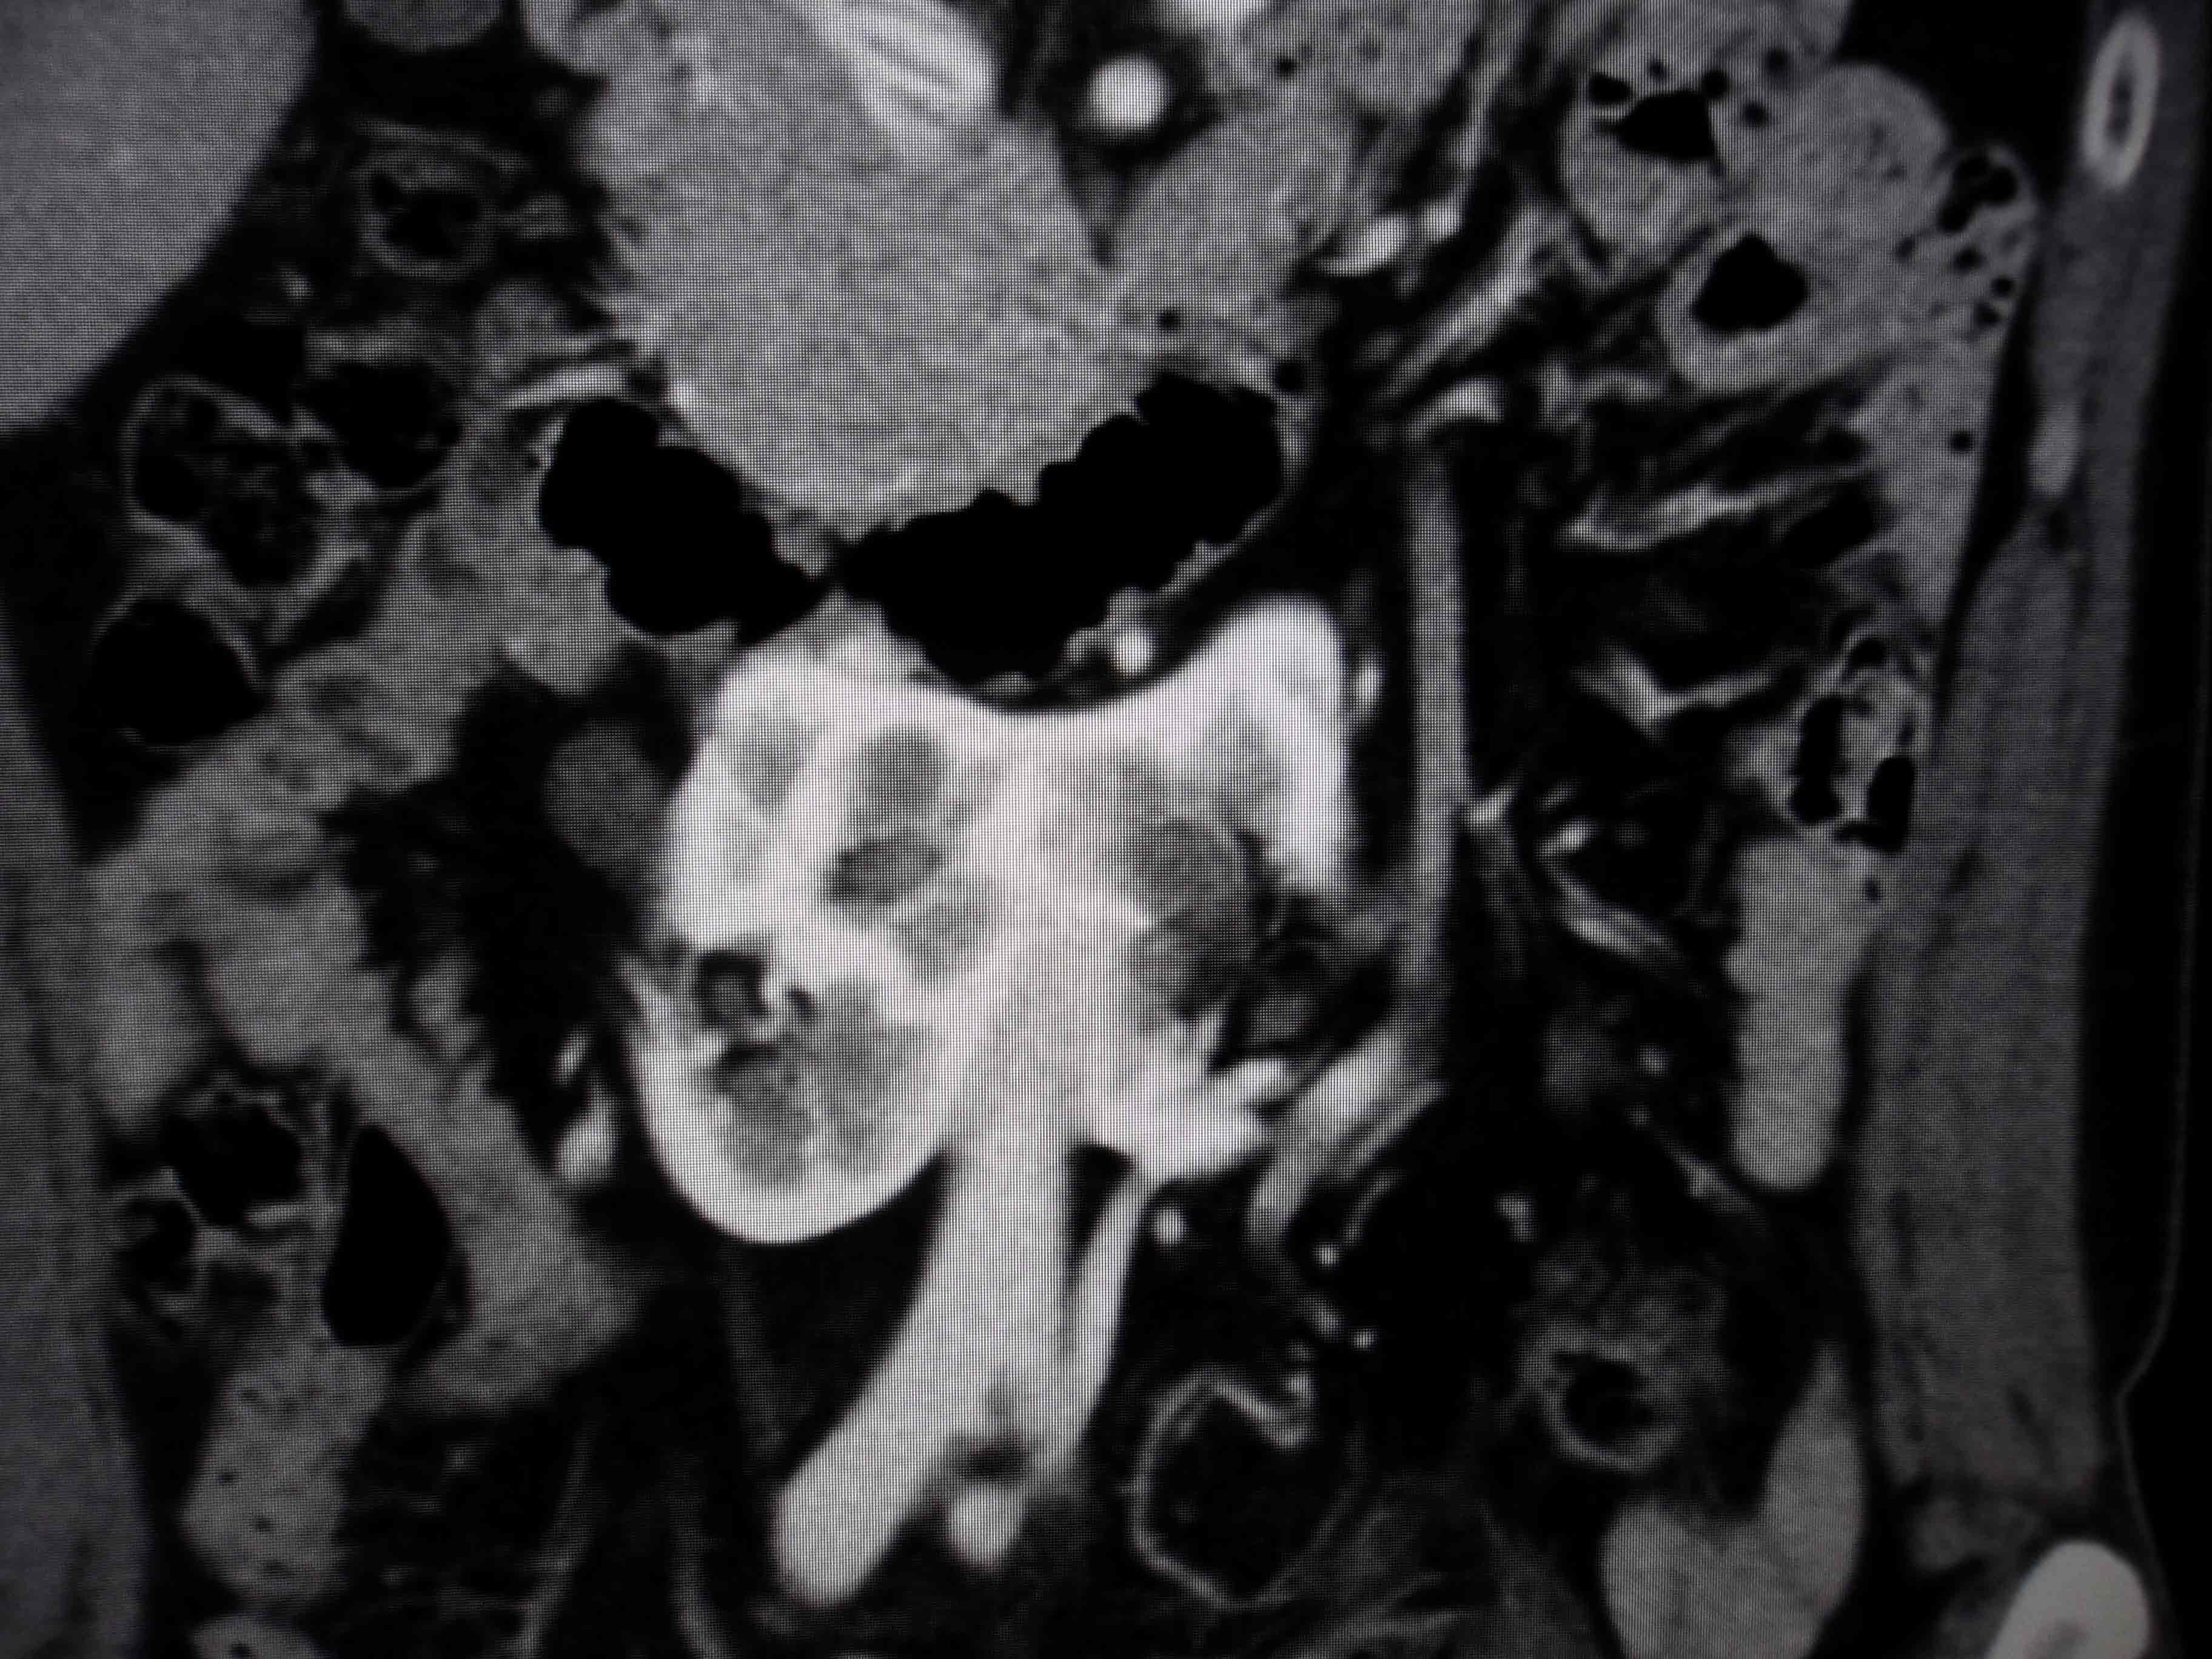

ºÎ½Å Á¾¾ç

»çÁøCT/MRI